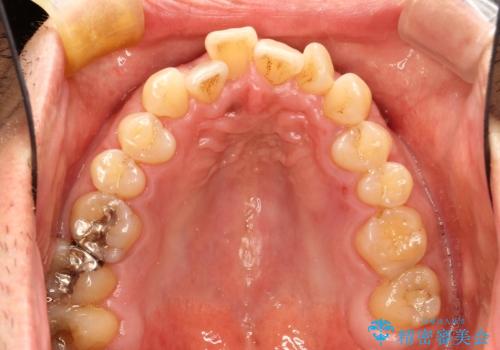

インビザライン invisalign ガタつきを治すマウスピース矯正

- 非抜歯・上顎臼歯遠心移動によるマウスピース矯正を計画した。

ガタつきを取り除くだけであれば非常に簡潔であるマウスピース矯正ですが、奥歯の位置関係の是正や、垂直的な歯の位置のコントロールなどが計画に含まれる場合、治療が難しくなってきます。